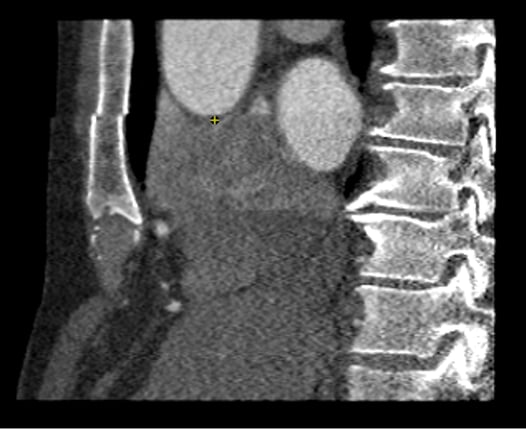

- Calcium scoring: A native (non-contrast) calcium scan helps quantify coronary calcification. This plays a key role in risk stratification and in planning further diagnostics or therapy. In cases of heavy calcification, a CCTA may be of limited diagnostic value and could be omitted. (Achenbach et al. 2012)

- Scan planning: Planning ensures all relevant coronary segments are captured while minimizing radiation dose. Use the native scan as a guide.

- Ensure the most superior coronary artery origin is fully within the scan range.

- Account for variants—e.g. vessels may arch upward or bend (“kinking”)—so include coverage for about 5 slices proximal to the first vessel (e.g. LAD) and 5 slices distal to the heart base, roughly 1–1.5 cm extra.